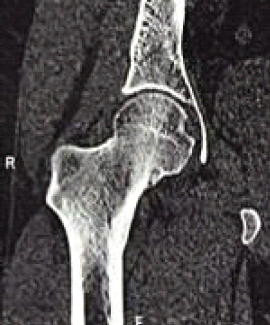

Osteoid Osteoma of the Femoral Neck Masquerading as Avascular Necrosis: A Diagnostic Dilemma and Management Success Story

Amit Kale , Sahil Chowdhary

………………………………p.151-155